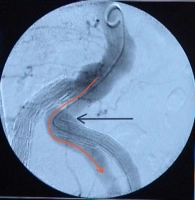

Type Ia endoleak: Due to migration of the endograft in the left internal iliac artery, sealing of the proximal landing zone is inadequate.